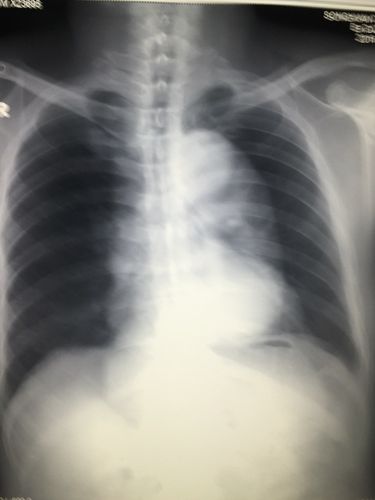

胸片提示少量气胸,幸亏坚持做了 ct,不然事情就糟了

胸片示降主动脉及主动脉弓明显扩张增宽.